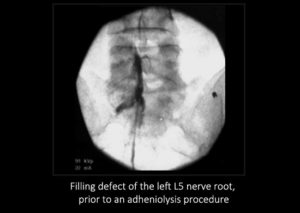

Scarring occurs after surgery, infection, bleeding and simply because we get older. Scar causes a number of problems which can lead to pain. Nerves in your spine need to move freely, just like the pistons in an engine, so that as you move, the nerves move. Scarring can tether the nerves, preventing this movement. Scars can also block epidural veins, causing them to become swollen and engorged. The swollen veins can then press on the nerves, causing the nerves to become inflamed and painful. Scarring can also prevent injections, like epidural injections, to work because the medication cannot get to the nerve. Percutaneous adhesiolysis works because it can break up scarring.

About 95% of the time, the procedure is done on an outpatient, one-day basis. It can also be done as a 3-day procedure. We do is to pass a special spring-wound catheter to the area of scarring. This catheter is soft enough to not damage the nerve. It is firm enough to be steerable.